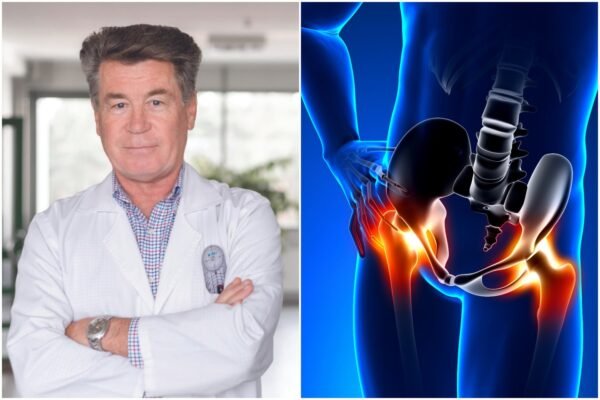

Gydytojas ortopedas atskleidžia, kaip sustabdyti kaulų retėjimą ir išvengti lūžių senatvėje

„Kaule juk nėra kraujagyslių, medžiagos jame keliauja dėl mikrodeformacijų, kurios sukuria savotišką siurblį. Tai būtų...